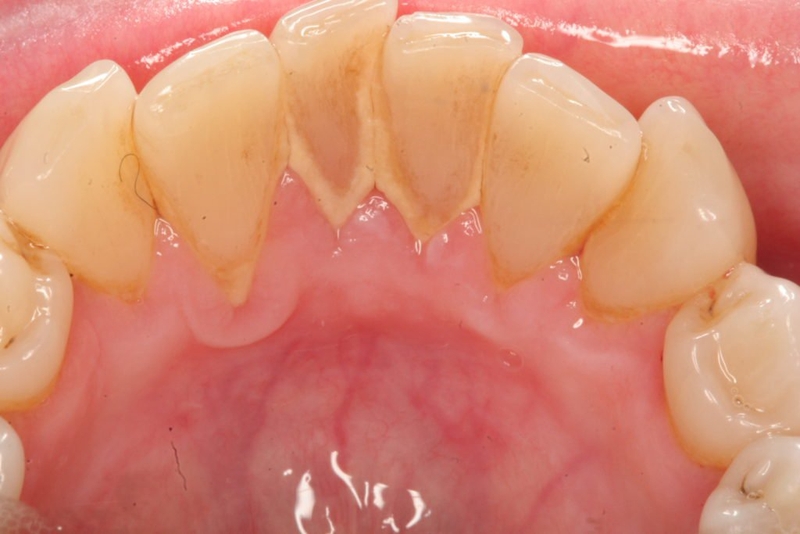

Trước khi tìm hiểu giá cạo vôi răng, cạo vôi răng bao nhiêu tiền thì đầu tiên bạn cần hiểu về vôi răng là gì. Vôi răng là các mảng bám dính chặt trên bề mặt răng. Chúng được tạo nên chủ yếu từ các mẩu vụn thực phẩm còn sót lại trên răng kết hợp cùng với xác vi khuẩn.

Thời gian đầu tích tụ, các mảng bám này thường khá mềm và theo thời gian chúng sẽ ngày càng cứng dần và bị vôi hóa hay cao răng. Vôi răng thường sẽ bám ở kẽ răng, vổ răng, dưới nướu răng của mình.

Vôi răng là các mảng bám dính chặt trên bề mặt răng